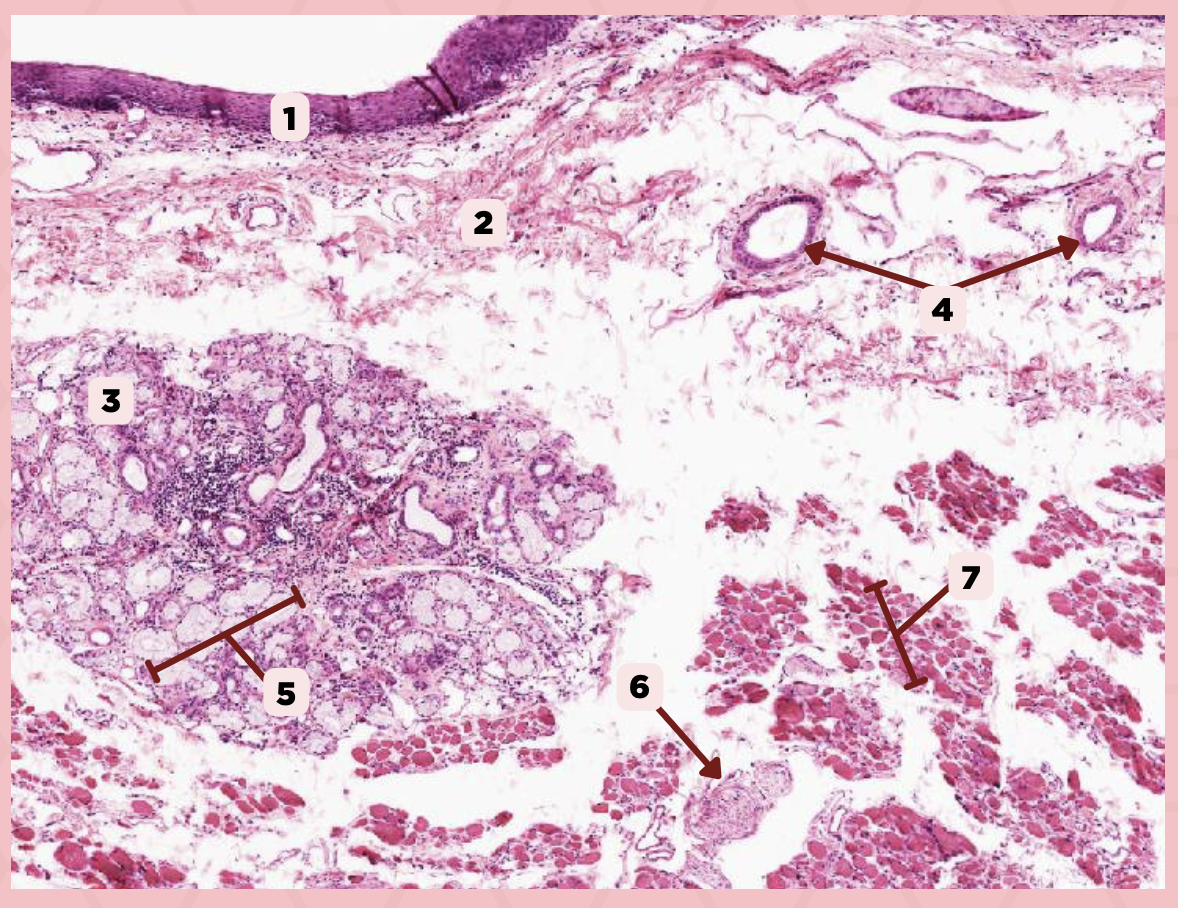

Lip

What specimen is being showed in the picture?

Epidermis

Identify the structure labeled as 1.

Dermis

Identify the structure labeled as 2.

Arrector Pilli Muscle

Identify the structure labeled as 3.

Hair Follicle

Identify the structure labeled as 4.

Sebaceous Glands

Identify the structure labeled as 5.

Lip

What is the specimen showed in the picture?

Epidermis

Identify the structure labeled as 1.

Dermis

Identify the structure labeled as 2.

Arrector Pilli Muscle

Identify the structure labeled as 3.

Hair Follicle

Identify the structure labeled as 4.

Sebaceous Glands

Identify the structure labeled as 5.

Lip

What specimen is showed in the picture?

Labial Glands (in the Mucosa)

Identify the structure labeled as 1.

Skeletal Muscle Cells

Identify the structure labeled as 2.

Lamina Propria

Identify the structure labeled as 3.

Mucosa

Identify the structure labeled as 4.

Lip

Cheek (Coronal Section)

Identify the specimen.

Hypodermis

Identify the structure labeled as 1.

Dermis

Identify the structure labeled as 2.

Epidermis

Identify the structure labeled as 3.

Cheek

Identify the specimen.

Sweat Glands

Identify the structure labeled as 1.

Dermis

Identify the structure labeled as 2.

Hair Follicle

Identify the structure labeled as 3.

Epidermis (Keratinzied Stratified Squamous Epithelium)

Identify the structure labeled as 4.

Cheek

Identify the specimen.

Vein

Identify the structure labeled as 1.

Hypodermis

Identify the structure labeled as 2.

Artery

Identify the structure labeled as 3.

Nerve

Identify the structure labeled as 4.

Cheek

Identify the specimen.

Mucosa

Identify the structure labeled as 1.

Lamina Propria

Identify the structure labeled as 2.

MALT

Identify the structure labeled as 3.

Blood Vessels

Identify the structure labeled as 4.

Buccal Glands

Identify the structure labeled as 5.

Nerve

Identify the structure labeled as 6.

Muscle Fascicles

Identify the structure labeled as 7.

Cheek

Identify the specimen.

Skeletal Muscle Fibers

Identify the structure labeled as 1.